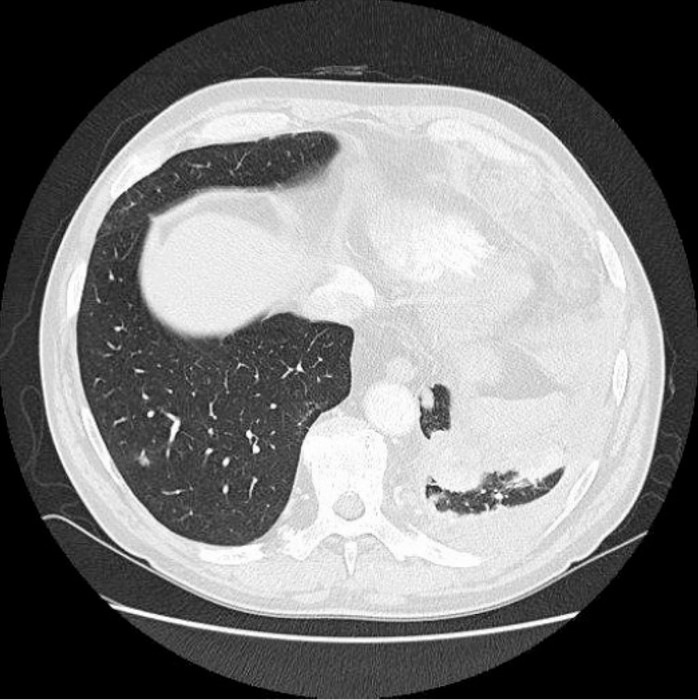

Das daraufhin veranlasste CT des Thorax zeigte kleinknotige Verdickungen an der Pleura und eine dorsal verbreiterte Pleura links, vereinbar mit Pleurakarzinose sowie weiterhin den Pleuraerguss linksseitig und die soliden Weichteilvermehrungen links dorsal mit Thoraxwandinfiltration und im ventralen Mediastinum, Differenzialdiagnose Weichteilmetastasen/Lymphknotenmetastasen (➥ Abb. 2).